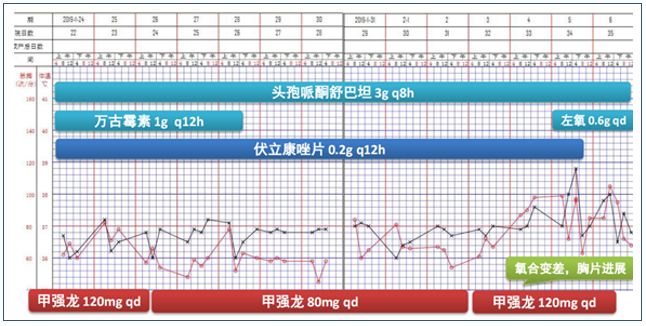

病情继续发展

根据患者临床表现及检查结果,再次调整治疗方案(图10)。

2019年1月25日,患者胸部CT显示双下肺实变较前有所吸收(图11)。

图11 2019年1月25日患者胸部CT

调整治疗方案

根据患者情况又调整了治疗方案(图13)。患者2月11日拔管脱机,再次出现高热,谵妄反复发作,胡言乱语,对外周刺激敏感,伴气促、低氧(SpO2:75%~85%)。

2019年2月1日患者胸部CT显示,上肺渗出进展(图14)。

调整治疗方案后,患者各项生命体征逐步改善(图15)。

2019年2月25日患者胸部CT示双肺病变较前吸收(图16)。